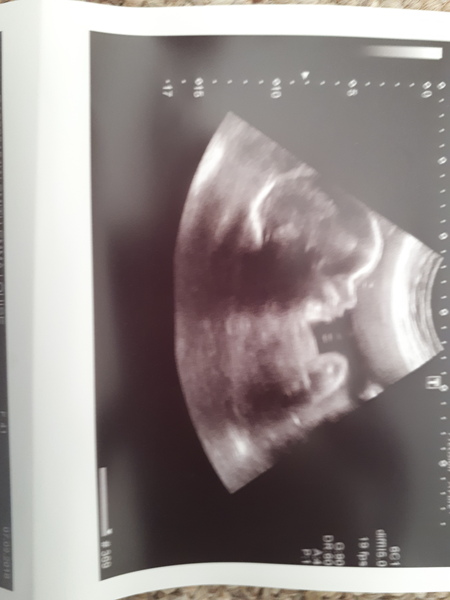

Had a growth scan this morning. She's still a girl (!) and despite everyone and their fucking aunty telling me my bump is tiny, she's measuring perfect for my dates.

During the scan we had a lovely view of her yawning and using my bladder as a trampoline!

Emwithme

She is absolutely beautiful!! 💖